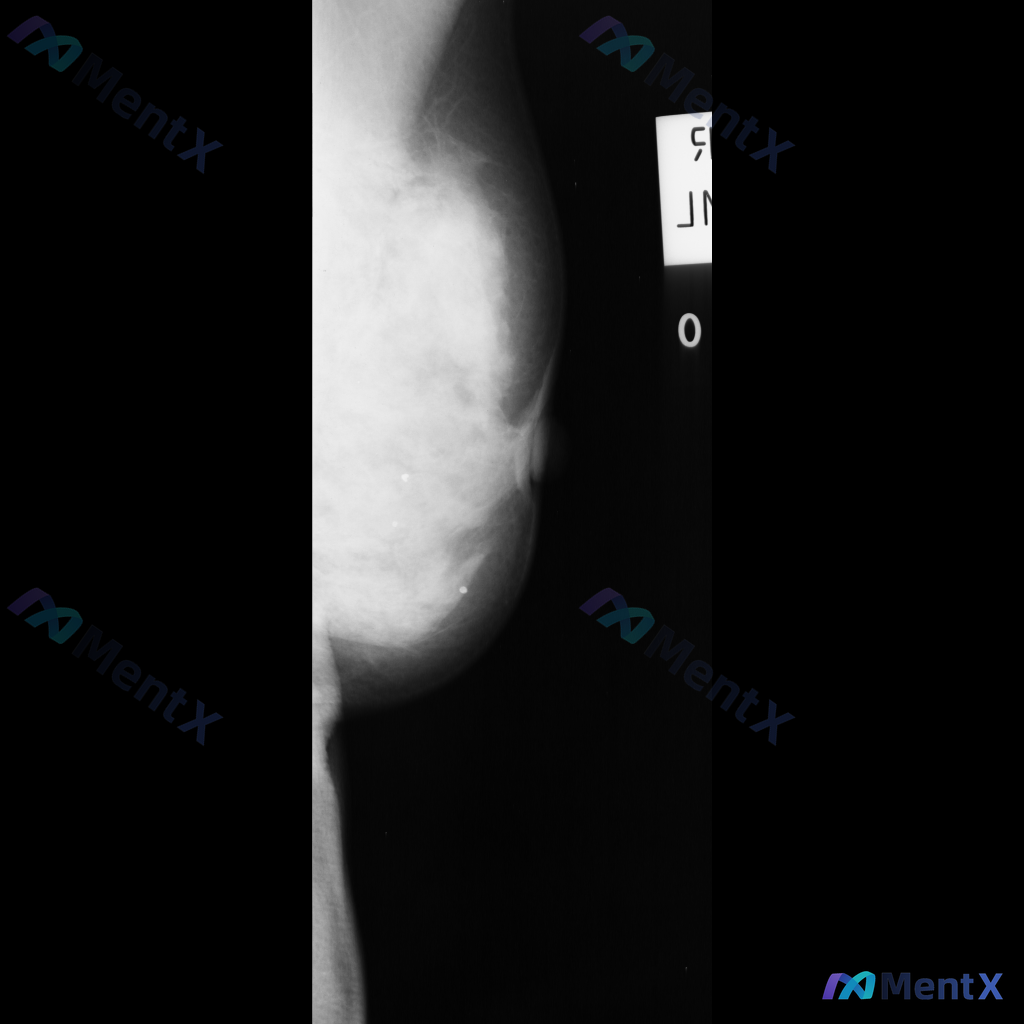

整理到一张乳腺钼靶影像的分析资料,先和大家同步一下核心表现: - 乳腺构成:不均匀致密型 - 主要异常:在乳腺中央偏上区域可见一个不规则形高密度肿块,边缘有毛刺样改变;围绕这个高密度影,周围的乳腺小叶和导管结构紊乱,向病灶中心牵拉。 目前暂时没有更多临床病史、查体或其他检查补充。想先问一下大家:单看...